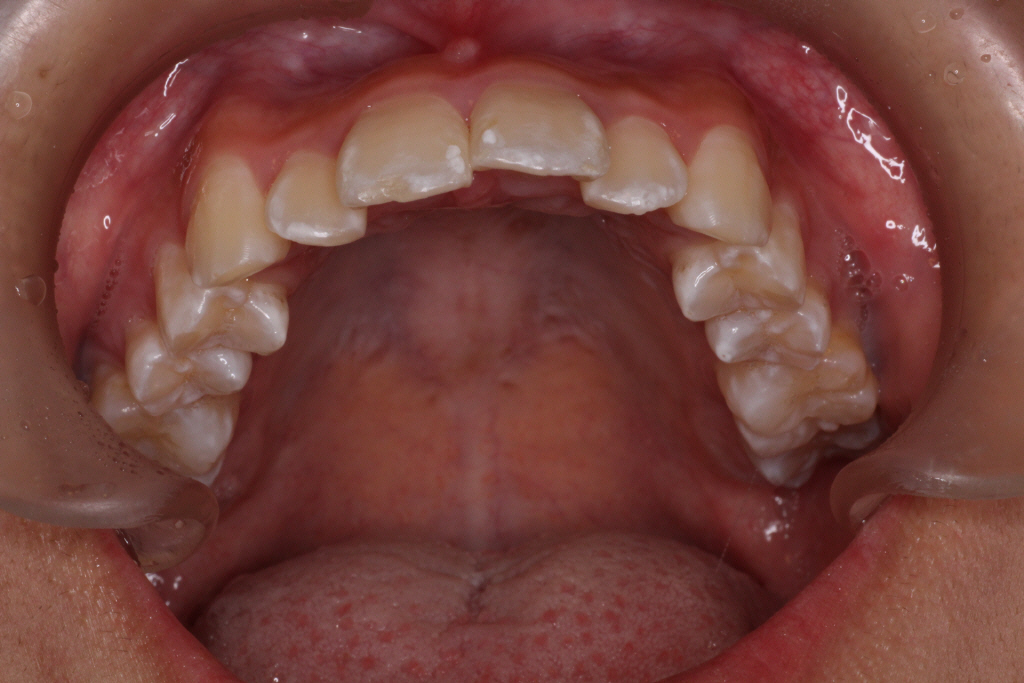

初診時の写真です。

前歯にはがたつき(叢生)がみられ、奥歯は上の歯と下の歯が1歯対1歯で噛んでいることがわかります。

つまり出っ歯の噛み合わせです。

診断:上顎前突・前歯部叢生